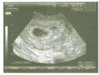

No a dzisiaj rano miała miejsce nasza pierwsza wizyta. Najpierw radosna - bo USG potwierdziło że mam fasolkę pod serduszkiem. Potem mniej radosna. Okazalo się że fasolka ma tylko 2,8mm (a to już 6tydzień), a w dodatku tuż obok niej znajduje się jakiś mały krwiaczek. Dostałam Duphaston na podtrzymanie ciąży i wizyta za 2tygodnie. Lekarz powiedział, żebyśmy się nie martwili, bo za 2 tygodnie może się okazać że wszystko jest OK, ale radził też nie dzielić się tą wiadomością z otoczeniem

. Boję się o moje maleństwo. Wklejam wam pierwszą fotkę fasolki, obok widać malutką czarną plamkę, to właśnie ten punkt który zaniepokoił lekarza